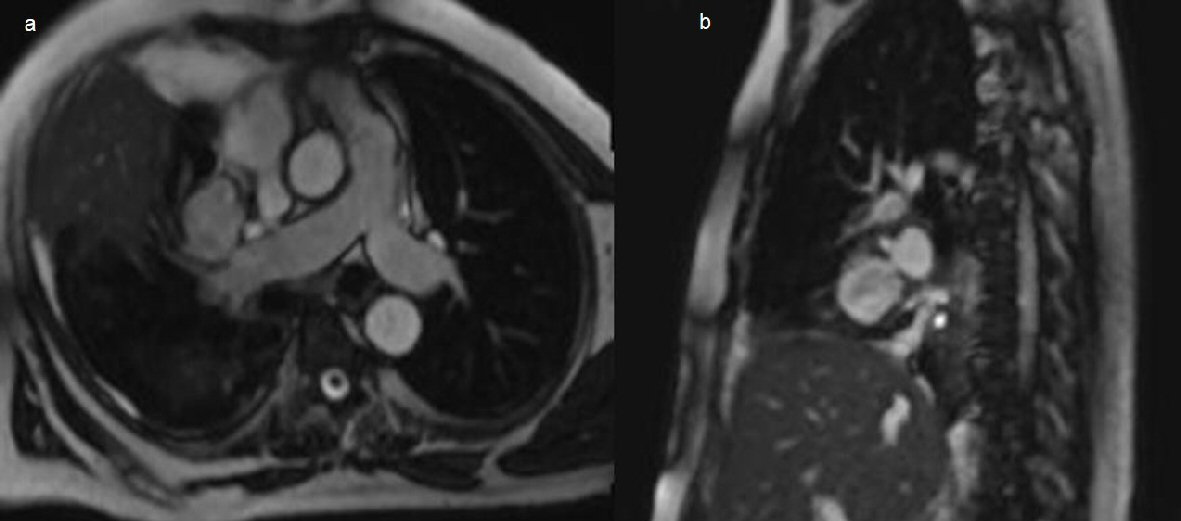

Two days after initial CT the right pleural effusion recollected, supported by CXR, a further 1 L of aspirate was drained from the intercostal catheter. Four days after the initial CT the patient remained febrile despite continued IV antibiotics and absence of ongoing drainage from the intercostal catheter. Ultrasound examination revealed small volume right pleural effusion of approximately 200 mL and repeat CXR showed residual costophrenic angle effusion and clearing of parenchymal changes in right lower lobe (Fig. 4). The intercostal catheter was removed and it was decided to perform a second CT chest to exclude ongoing effusion or pneumothorax. Repeat CT chest on day 12 of the patient’s admission revealed a large, rounded contrast abnormality contiguous with the right medial segmental branch of the middle lobe pulmonary artery, most likely representing a pseudoaneurysm (Fig. 5). This was a new finding as compared to CTPA examinations from 12 months prior. When compared to the previous CT 4 days prior the mass had increased in size by 5 mm on the coronal plane. In order to define the contrast abnormality seen on CT, a MRI chest was ordered (Fig. 6). A large round pseudoaneurysm arising from the right medial segmental branch of the middle lobe pulmonary artery was confirmed, and steady state free precession sequences imaging demonstrated flow between the right pulmonary artery and the lesion.

![]() Click for large image | Figure 6. (a) Chest axial oblique non contrast MRI steady state free precession sequences showing a right pulmonary artery pseudoaneurysm arising from the medial segmental branch of the middle lobe, measuring 37 × 32 × 37mm. (b) Sagittal imaging through the pseudoaneurysm confirming connection to the right pulmonary artery. |